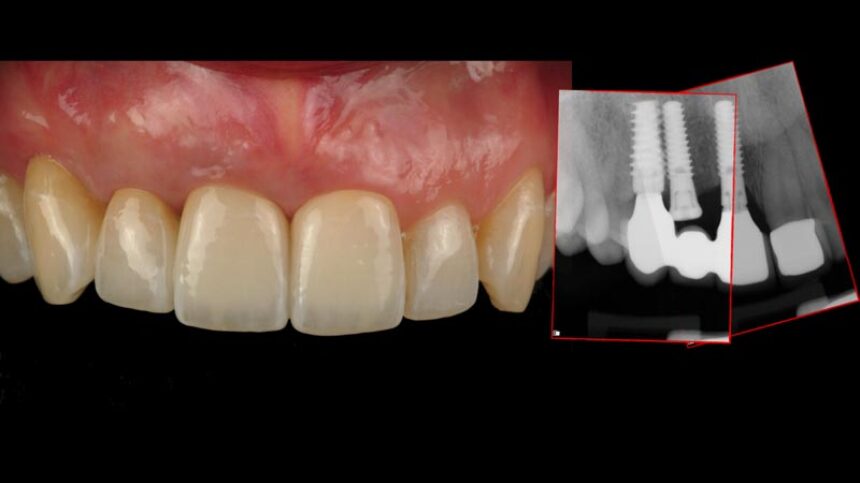

· διαχείριση μαλακών ιστών σε άμεση τοποθέτηση εμφυτεύματος

· επιλογή κατάλληλης χρονικής στιγμής, διαδοχική σειρά βημάτων & επιλογή σημείου

· τεχνική λήψης μοσχεύματος από το έπαρμα της γνάθου, χειρισμός & διαμόρφωση ιστών